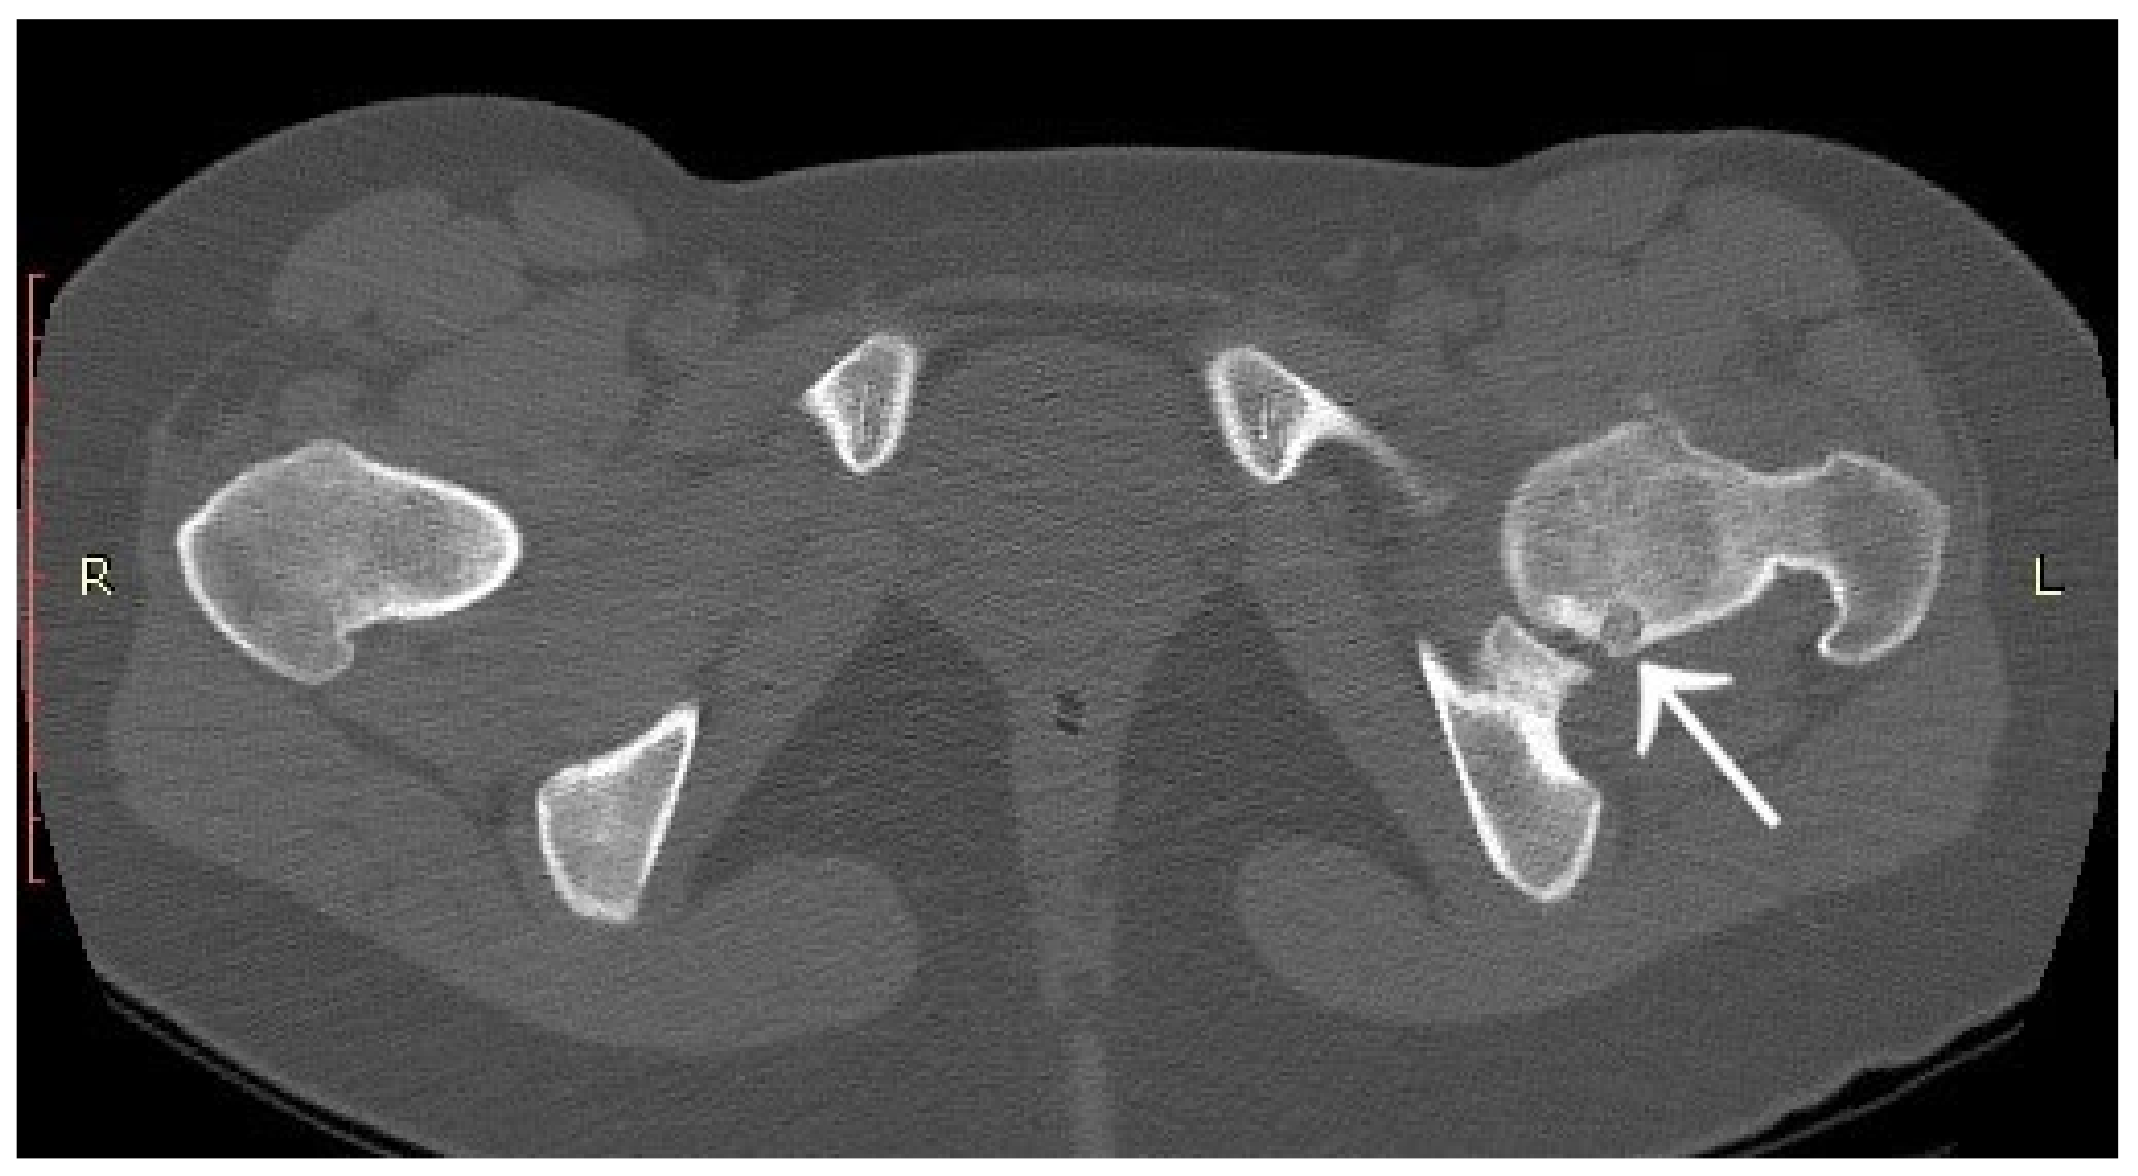

3.1. Case 1: OO Masking as Femoroacetabular Impingement (FAI)

3.2. Case 2: Example of an Incorrect Therapeutic Path of OO